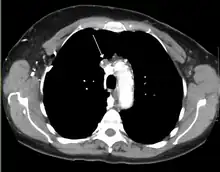

Thrombosis of the superior vena cava caused by an indwelling central venous catheter which caused superior vena cava syndrome

A CT image showing compression of the right hilar structures by cancer

The main techniques of diagnosing SVCS are with chest X-rays (CXR), CT scans, transbronchial needle aspiration at bronchoscopy and mediastinoscopy.[6] CXRs often provide the ability to show mediastinal widening and may show the presenting primary cause of SVCS.[6] However, 16% of people with SVC syndrome have a normal chest X-ray. CT scans should be contrast enhanced and be taken on the neck, chest, lower abdomen, and pelvis.[6] They may also show the underlying cause and the extent to which the disease has progressed.[6]